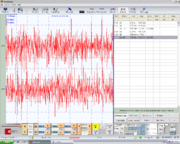

| 13:33, 18 August 2023 | Jaw jerk in capsaicinica.bmp.png (file) |  |

77 KB | Gianni | 1 | |